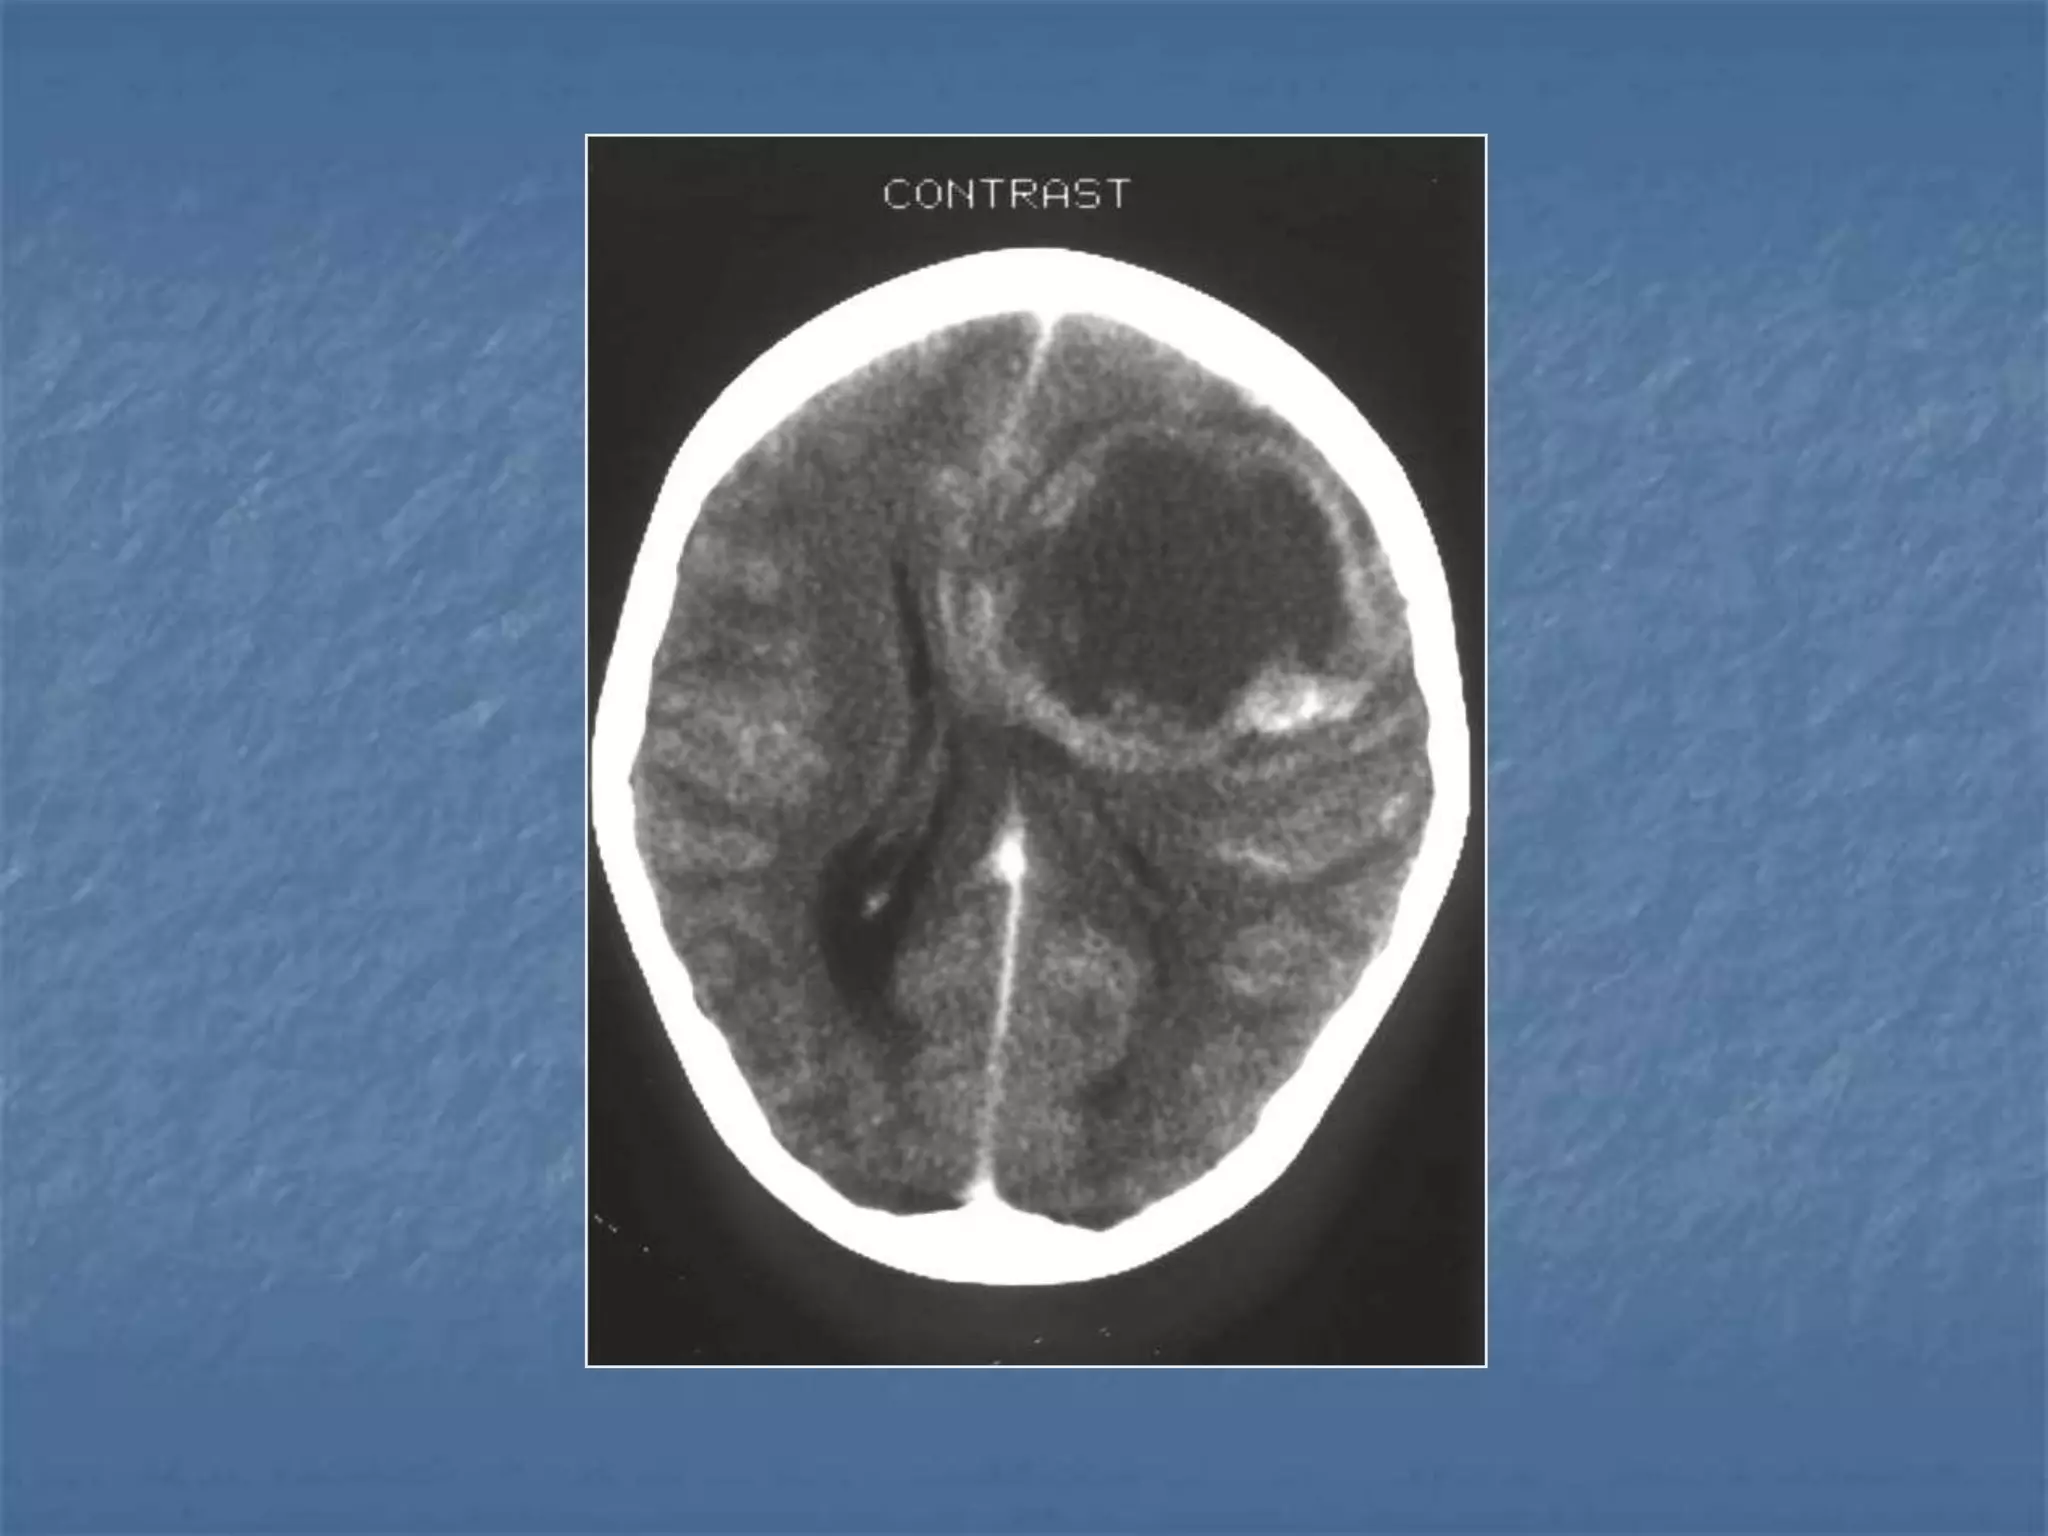

Subdural Empyema

 Subdural empyema is usually due to

meningitis, sinusitis, trauma or prior surgery.

It is a neurosurgical emergency. Subdural

empyema leads to rapid clinical deterioration,

especially if it is due to sinusitis. On CT it

appears as an isodense or hypodense extra-

axial mass. It has a lentiform or crescentic

shape.

The margin of collection often enhances with

contrast material administration due to the

presence of granulation tissue or subjacent

cortical inflammation.

Extra-axial CNS Infection

 Extra-axial CNS infections can cause epidural

abscess or subdural empyema. Extra-axial CNS

infections account for 20-30% of CNS infections.

Fifty percent of extra-axial infections are

associated with sinusitis, usually frontal sinusitis.

The infection occurs by direct extension or septic

thrombophlebitis. Thirty percent of extra-axial

infections occur post-craniotomy. Finally, 10-15%

of extra-axial CNS infections are related to

meningitis. CT findings include a focal fluid

collection usually with an enhancing margin in a

subdural or epidural location.

Epidural Abscess Subdural

Empyema

 Notice the rim enhancing

epdural fluid collection

(arrowheads)

).